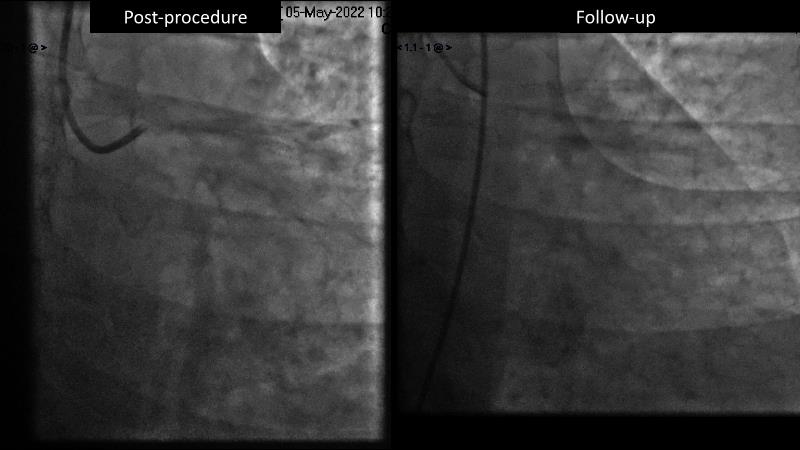

Consult this session to understand the technology and scientific evidence of the novel sirolimus drug-coated balloon, to learn its utility for PCI in a variety of lesion and patient subsets and to understand the evidence and outcomes in real-world patients.

- To learn the utility of the DCB for PCI in a variety of lesion and patient subsets

- To understand the evidence and outcomes of this DCB in real world patients